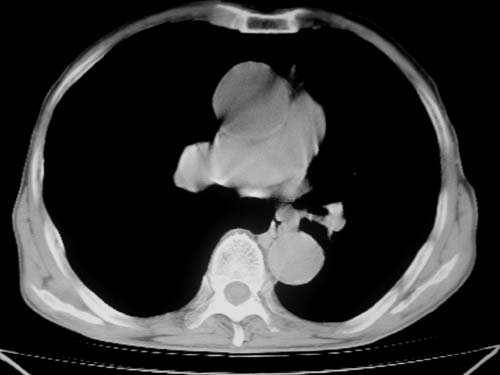

标题: CT19736:男,76岁,咳嗽,胸痛 [打印本页]

标题: CT19736:男,76岁,咳嗽,胸痛

周围型肺癌?坏死性肉芽肿?

支持左上肺周围型肺癌性并空洞形成伴胸椎转移。

左上沟癌空洞形成并胸椎转移。

考虑癌性空洞并胸椎转移。

空洞内壁有多发结节,支持癌性空洞。